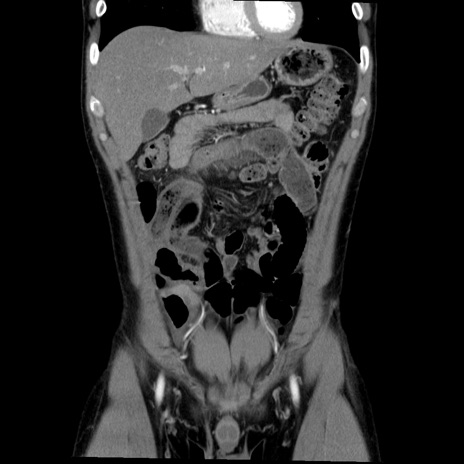

症例36(冠状断像)

【症例】20歳代 男性

【主訴】心窩部痛

【現病歴】今朝より上腹部痛あり。一旦軽快していたが再度出現したため救急要請。昨日夕に白身の魚を含む刺身を食べた。

【身体所見】BP 136/89mmHg、HR 74/min、BT 37.0℃、腹部:膨満、軟、心窩部に圧痛あり。反跳痛なし、筋性防御なし、腸雑音やや亢進あり。

【データ】WBC 17700、CRP 0.48